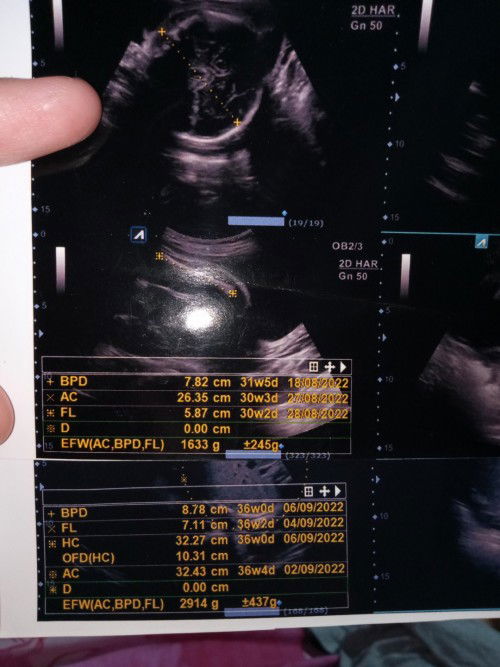

TENTANG HPL dan USIA JANIN

mau tanya bund... ini gmna yaa saya bingung. keterangan USG yg atas itu saya periksa tgl 14 Juni 2022, katanya sudah masuk 31w5d. trus yg bawah itu baru kemarin saya USG tgl 02 agustus 2022, HPL nya jadi beda, terus kok usia janin masih 36w0d. kalau di ikutin dari USG yg di atas (14 Juni 2022 usia janin 31w5d, saya hitung manual melalui kalender seharusnya besok sudah 38w) gmn yaa bund, saya kurang ngerti. dokter jelasin juga saya kurang ngeh 😞